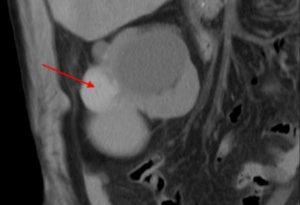

- Компьютерная томография — самый точный метод, но и самый дорогой. Является методом выбора для принятия решения о возможном раковом процессе, оценки кровоснабжения образования, определения габаритов, контуров, распространения образования внутри и вне органа;

- Компьютерная томография.

- Компьютерная томография — один из самых современных методов, который поможет разглядеть все подробности внутреннего строения почки с помощью послойных снимков. Для исключения наличия злокачественного процесса может быть дополнительно назначено внутривенное введение контрастного вещества. Если обнаруживаются перегородки, многокамерность, чрезмерное уплотнение кисты или отложение кальцификатов, то это может быть указанием на онкологическую опухоль.

| КТ | Дает пространственное отображение почки и дает возможность тщательно изучить структуру кисты |